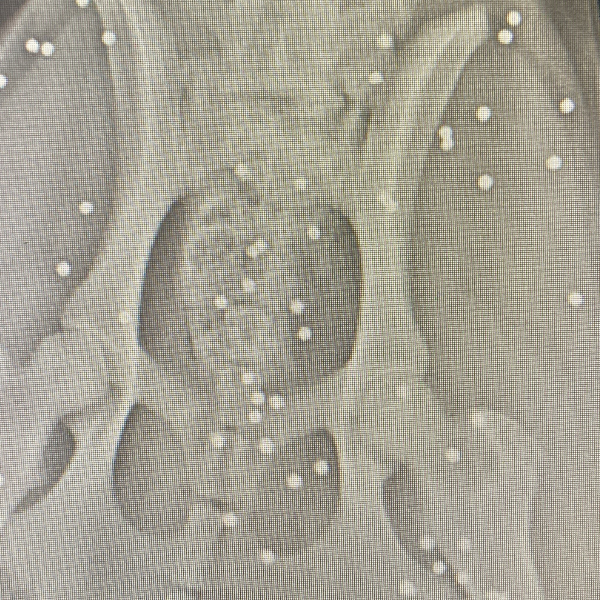

Köpeğin durumu hakkına açıklama yapan Veteriner Mustafa Gülcü, "Köpek bize silahla yaralanma şikayetiyle geldi. Biz hemen ilk müdahalesini yaptık. Ardından röntgen çektik, incelediğimizde çok sayıda saçmaya rastladık. Yakın mesafeden sıkılsa sinirlerine zarar verebilirdi" sözlerine yer verdi.

Yaşananları anlatan Gülhan Tünay, "Sabah saatleriydi iki el silah sesi duydum. Ardından köpeği acı içerisinde buldum. Eşime seslenerek eyvah köpeği vurdular dedim. Köpek arka tarafı kanlar içinde geldi. Seçim gecesi de bir köpek vurulmuştu, o köpek şuan ampute oldu. Veterinere söyledim gelip aldılar. Daha sonra polisi aradım ve köpeği vuran kişiden şikâyetçi oldum. Röntgen görüntülerine baktığımızda köpeğin arka kısmı tamamen yok. Kaç tane saçma olduğunu bilmek zor. Şuan durumu çok iyi değil, ilk getirdiğimizde hayati tehlikesi vardı. Şuan serum takılı biz de bekliyoruz. İnşallah özürlü kalmaz. Ne hissettiğini bilmiyorum. İnsanların artık silahlanması önlensin istiyorum" dedi.